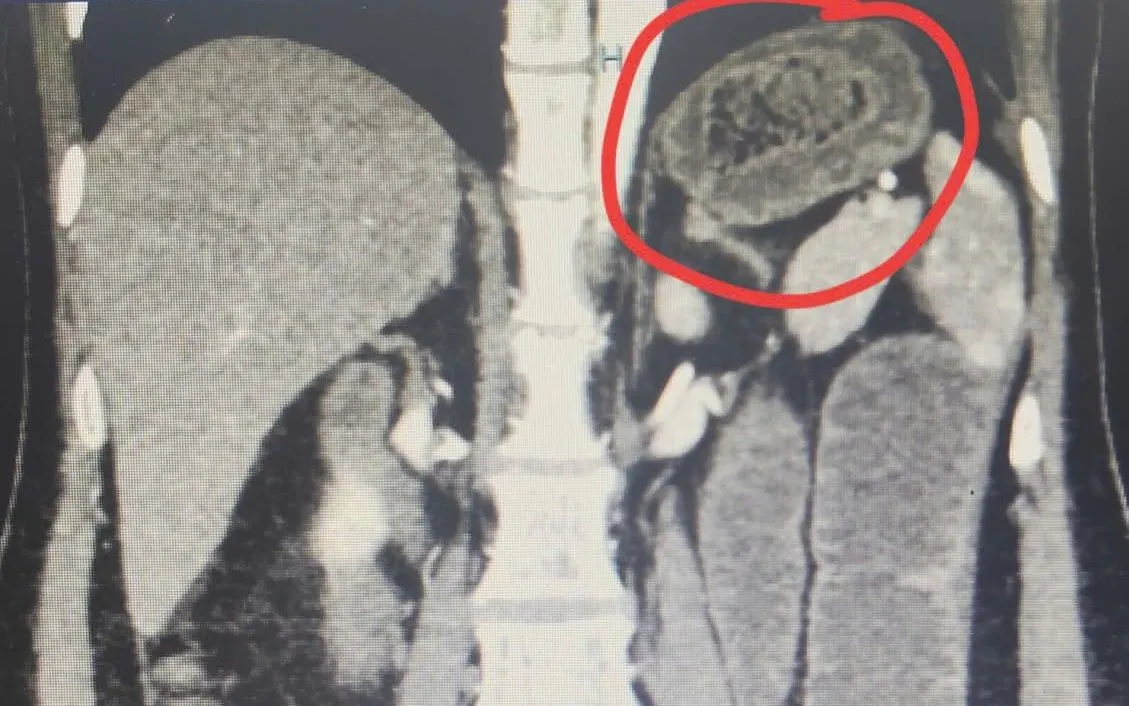

Qua thăm khám lâm sàng và chẩn đoán hình ảnh, các bác sĩ phát hiện bệnh nhân có một khối bã thức ăn lớn trong dạ dày và một khối khác gây tắc ruột non. Trường hợp này phức tạp do tổn thương xuất hiện ở hai vị trí, đòi hỏi chiến lược điều trị phối hợp nhiều chuyên khoa nhằm xử lý triệt để nhưng vẫn bảo đảm an toàn, hạn chế xâm lấn.